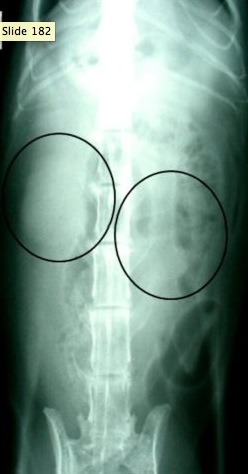

(Where are the Kidneys)

(Dog kidney)

(cat kidney)

(easier to palpate kidneys in cats than in dogs)